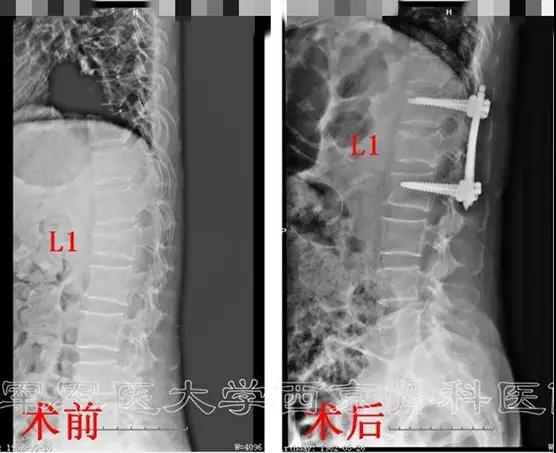

术前X线正侧位片

术后X线片正侧位及三维CT